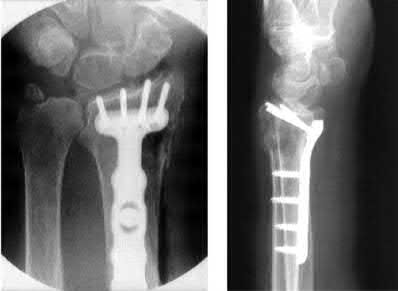

A 64-year-old woman is thrown off a horse, sustaining the injury shown in Figures A and B. She undergoes surgical fixation as seen in Figures C through E. What is the most commonly reported complication of this procedure?

The patient in the scenario has a 2-part proximal humerus fracture treated with a locking plate as seen in Figures A-E. The most common complication with the use of this implant is screw penetration. The terms screw cut out and penetration are often used interchangeably in the literature with cut out appearing more frequently in reports regarding intertrochanteric fractures.

Owsley et al retrospectively reviewed 53 proximal humerus fractures treated with locking plates and the same post-operative protocol. The most common complication was screw cut out or penetration, followed by varus displacement. They concluded that 3 and 4-part fractures in patients over 60 years have a higher incidence of failure.

Agudelo et al retrospectively reviewed 153 patients at a level-one trauma center treated with proximal humerus locking plates, investigating modes of failure for the implant. They determined that varus malreduction (head-shaft angle